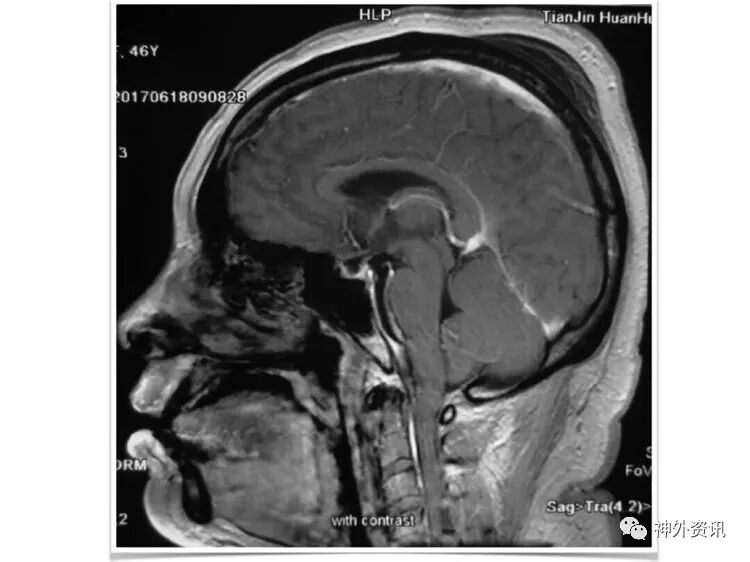

笔者的理解是:颈总动脉分叉部,位于下颌角水平以上(含下颌角水平)。此病例,颈内动脉狭窄部位,位于下颌角水平以上,接近颅底,属于高位CEA。